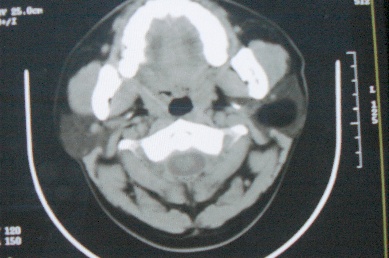

ct10755,男,28岁。发现左侧腮腺区肿块几年,今要求ct检查。左侧腮腺区低密度影,ct值-153hu。

左侧腮腺区囊状低密度影,ct值-153hu,考虑腮腺脂肪瘤。

病灶为一边界清晰脂性区,其内未见实质性组织.支持考虑:左侧腮腺脂肪瘤可能性大.

ct能定性的良性肿瘤不多,对脂肪瘤的诊断是比较有把握的,加大窗宽还可以看到里面有分隔

ct值-153hu,腮腺脂肪瘤。